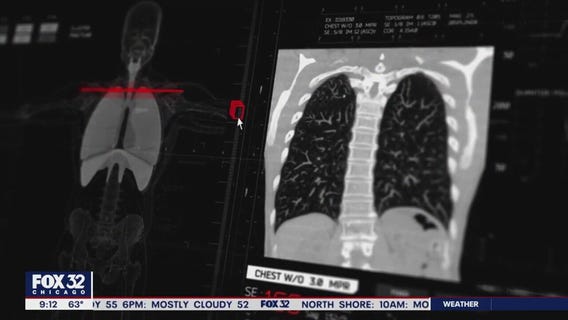

Roseland Hospital expands mammography facilities to improve breast cancer survival chances

Roseland Hospital on Chicago's Far South Side celebrated National Breast Cancer Awareness Month by focusing on more than just raising awareness.